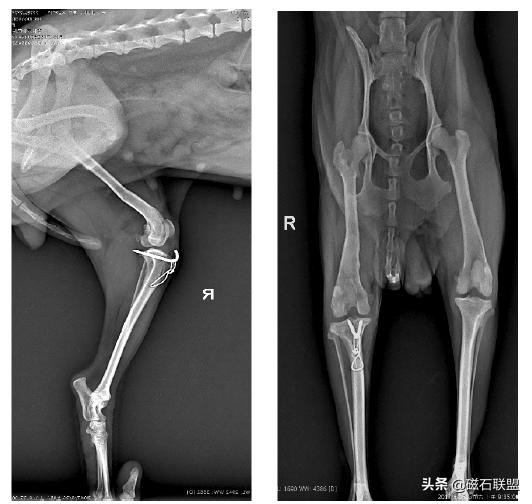

X射线检查:

影像学检查诊断为右后肢髌骨外脱位,与主人协商后决定进行手术。

★术后影像

手术后2小时即恢复清醒,一个月后基本恢复正常行走,取出钢针后恢复较为良好。